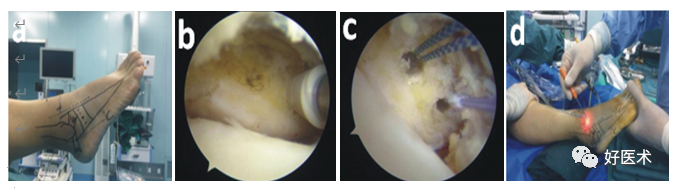

图片

上图为关节镜下改良Broström术式治疗慢性踝关节外侧副韧带损伤。a.患者术前绘制体表标志;b.在腓骨远端置入锚钉;c.两颗锚钉各带一根线;d.使用肝针或suturelasso进行过线(来自参考文献1)

图1术前标记解剖标志及“安全区”(A);使用刨削刀头和射频消融清理外侧关节囊及韧带病损处,关节镜下确定锚钉的安放位置,前外侧通道通过套管在腓骨远端前表面拧入锚钉(B,C);使用拉索“outside-in”技术尽可能穿过支持带和关节囊后从通道退出引出锚钉线(D)(来自参考文献8)